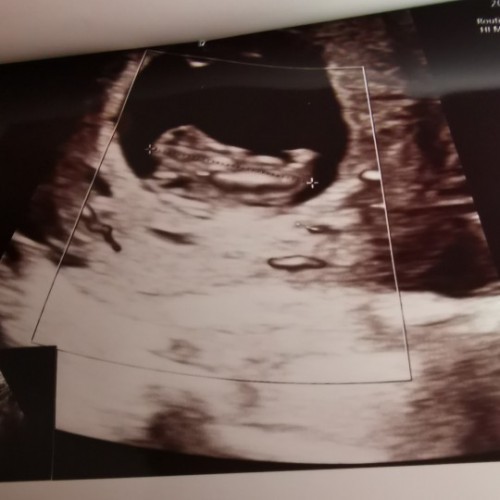

10wค่ะ

VIP Member